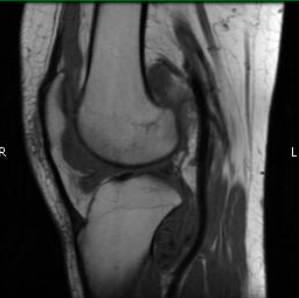

Radiographic imaging is used to help form a diagnosis of PVNS. These include X-Ray, MRI, CT and Bone Scans

An example of an MRI is shown.

MRI PVNS